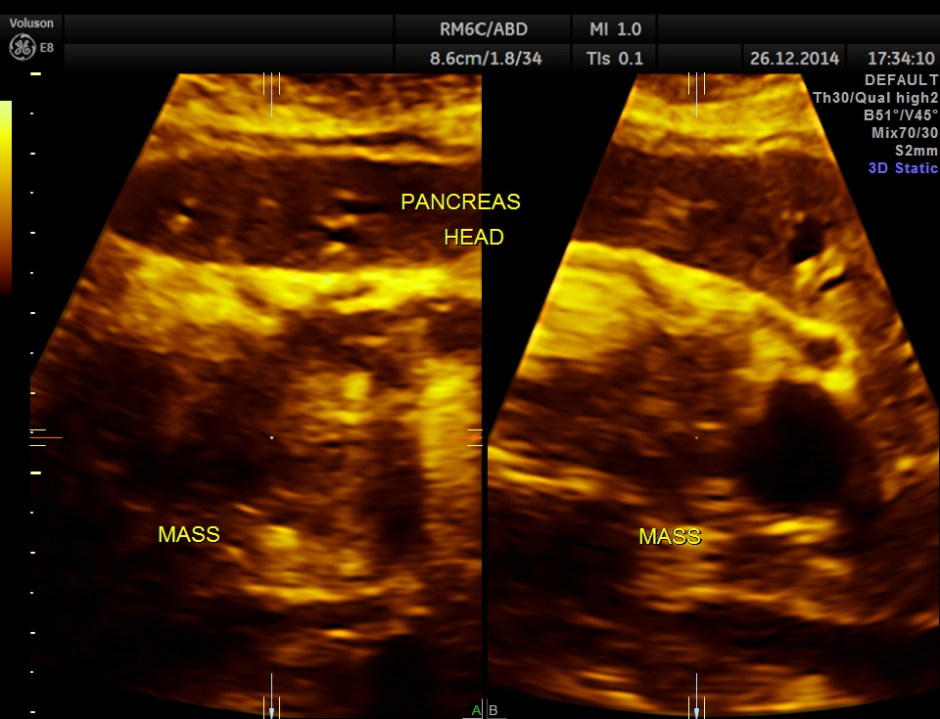

3d reconstruction of the head of the pancreas

This was a case of Carcinoma of the head of the pancreas , causing biliary obstruction and also pancreatic ductal obstruction , with possible peritoneal deposits.